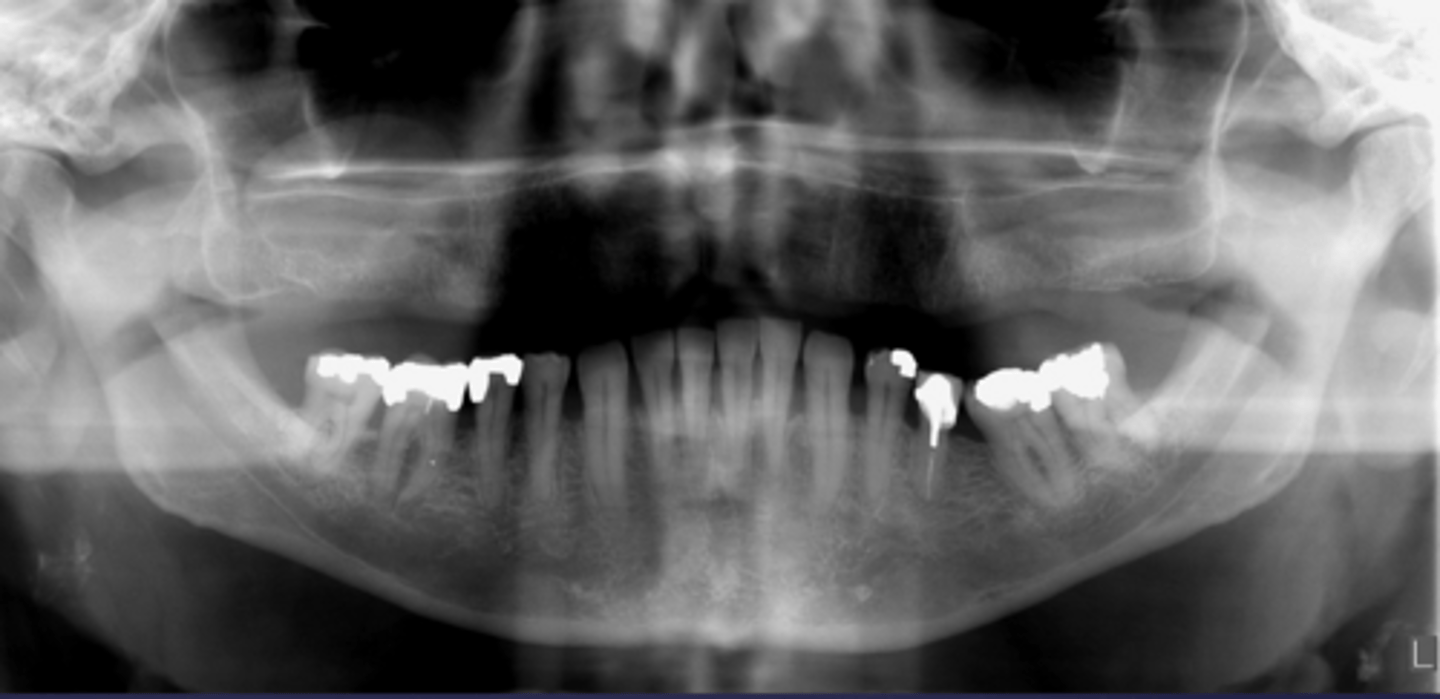

how would you describe this lesion? (not the giant cavity btw)

A. defined, corticated, periapical radiolucency causing loss of lamina dura and PDL space on #6-7

B. defined, non-corticated, periapical radiolucency causing loss of lamina dura and PDL space on #6-7

C. ill-defined, circular radiolucency located above tooth #7

D. well-defined, corticated, radiopacity

- Also note epicenter located above apex # 7 which has large dental caries.

What category would this lesion be part of?

Inflammation/benign

all of the following could be a differential diagnosis for the following lesion EXCEPT?

A. radicular cyst

B. Periapical granuloma

C. apical rarefying osteitis

D. renal osteodystrophy

what category would this lesion be classified into?

inflammatory/benign cystic